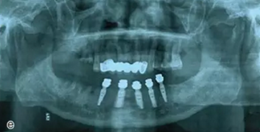

本案例為78歲男性患者,下頜義齒活動、固位差,口內(nèi)有殘根。患者要求進(jìn)行種植義齒修復(fù)。

術(shù)前拍攝錐形束CT,進(jìn)行三維重建和種植方案規(guī)劃。從CT圖像中可以看出頜骨內(nèi)有骨島和殘根,為避免種植體植入骨島區(qū),考慮在兩側(cè)頦孔區(qū)種植4~5顆種植體,采用套筒冠進(jìn)行即刻修復(fù)。從重建的結(jié)果中可知前牙區(qū)牙槽嵴呈刀刃狀。種植方案為:對前牙區(qū)牙槽嵴進(jìn)行截骨修整,并在兩頦孔之間的區(qū)域內(nèi)植入5顆種植體。

圖15 種植方案的規(guī)劃:a.患者的CT圖像的截面圖,圈紅處為骨島;b.患者摘掉活動義齒后的下頜;c.患者上下頜骨的CT三維重建;d.下頜骨截骨后模擬植入5顆種植體